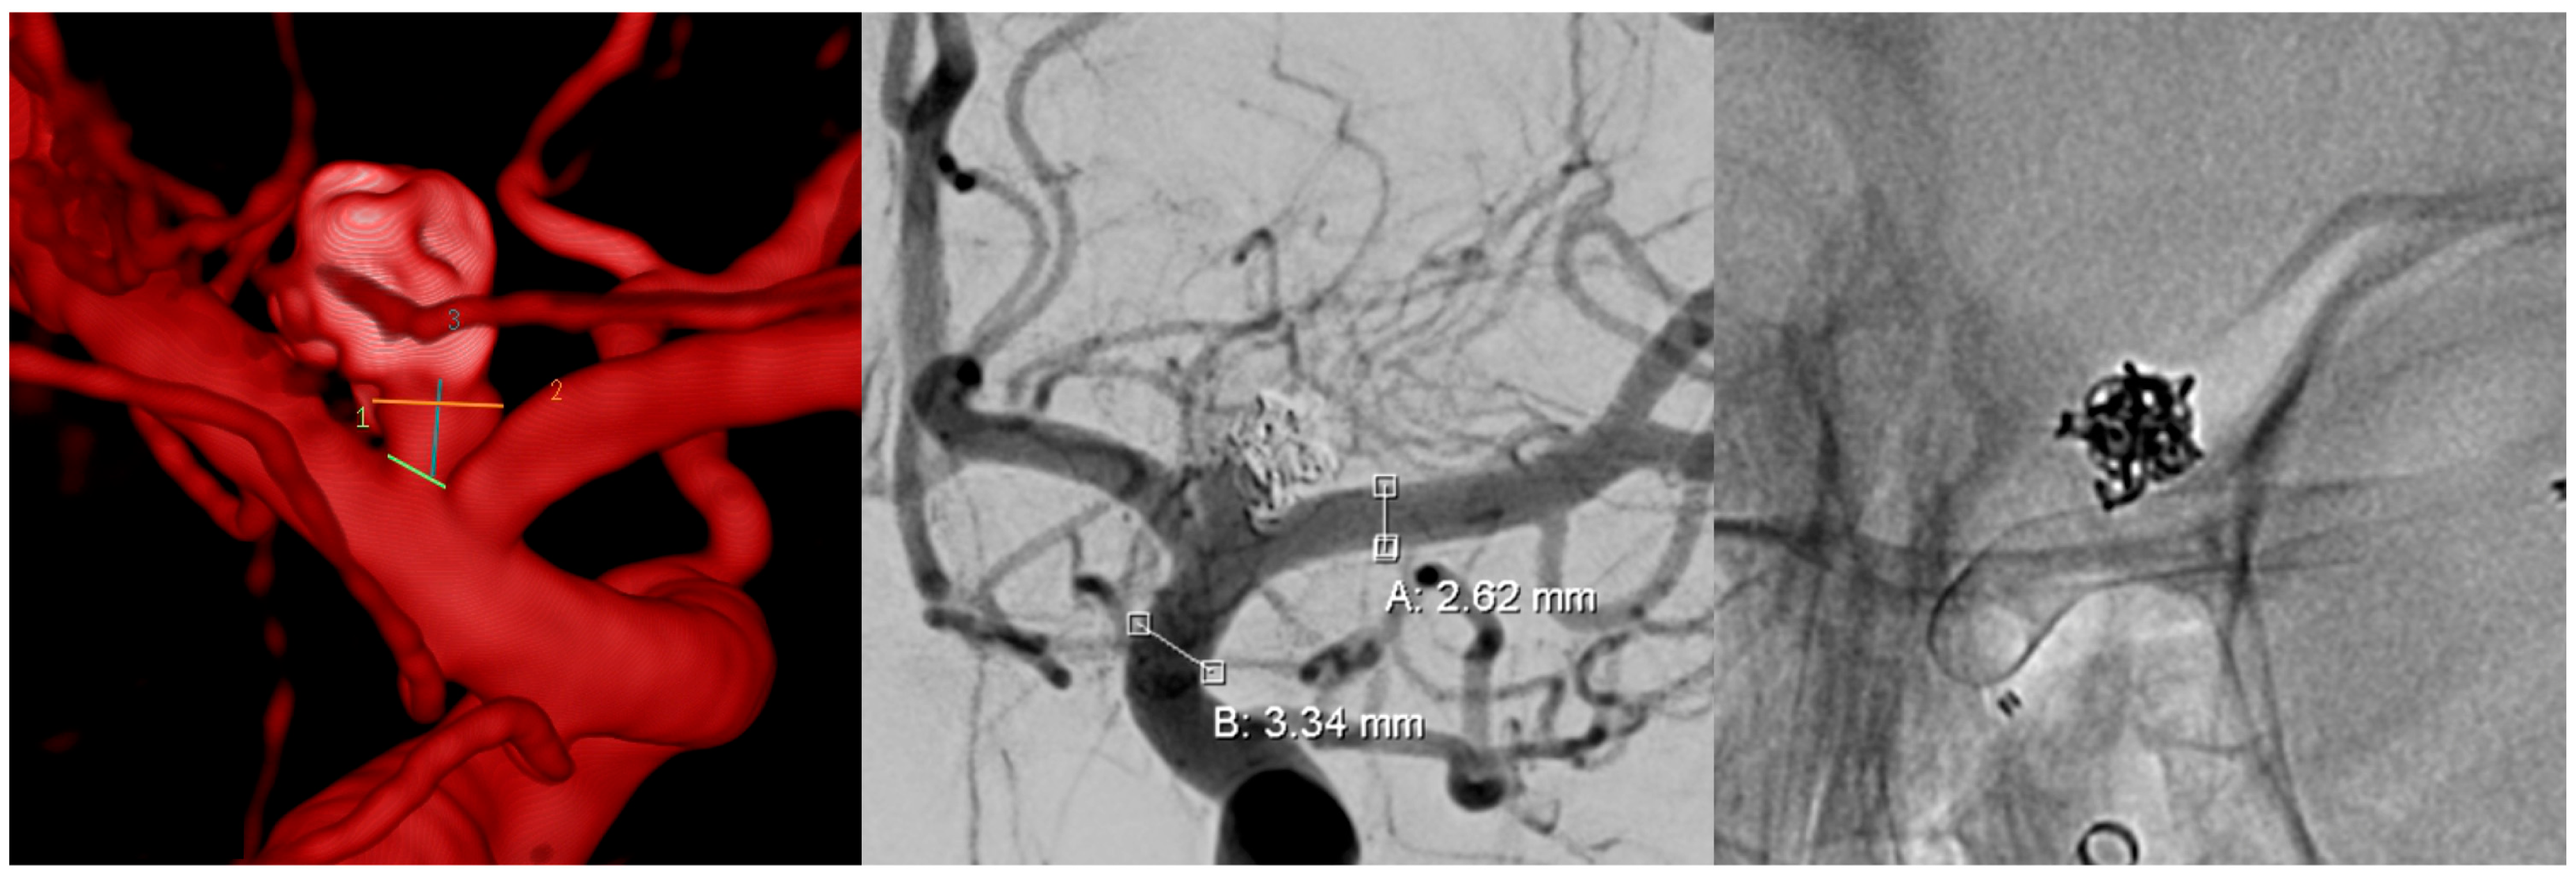

| 27 | Female | 27 | Left M1, ruptured saccular aneurysm, P&P | 3.5 | 2.8 | SVB 3.25 × 20 | 0.45 mm, 16% | >85% of the proximal (ICA) and >60% of the distal landing zone (M1) | 3 weeks | 10% | >95% |